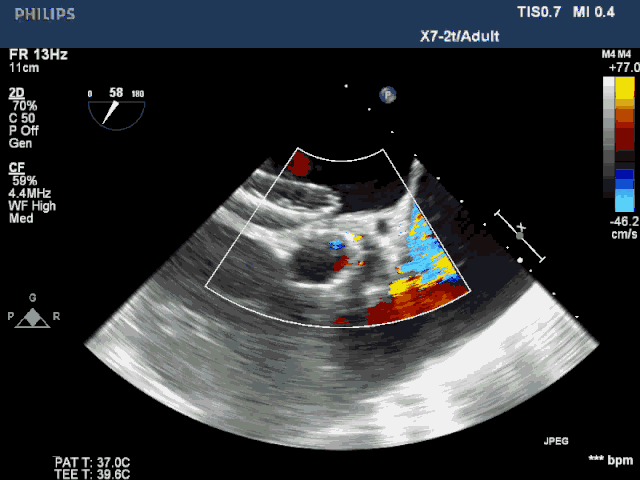

术后超声